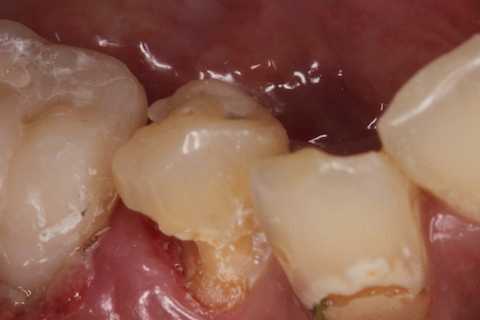

残根上のCR8 2025.10.28